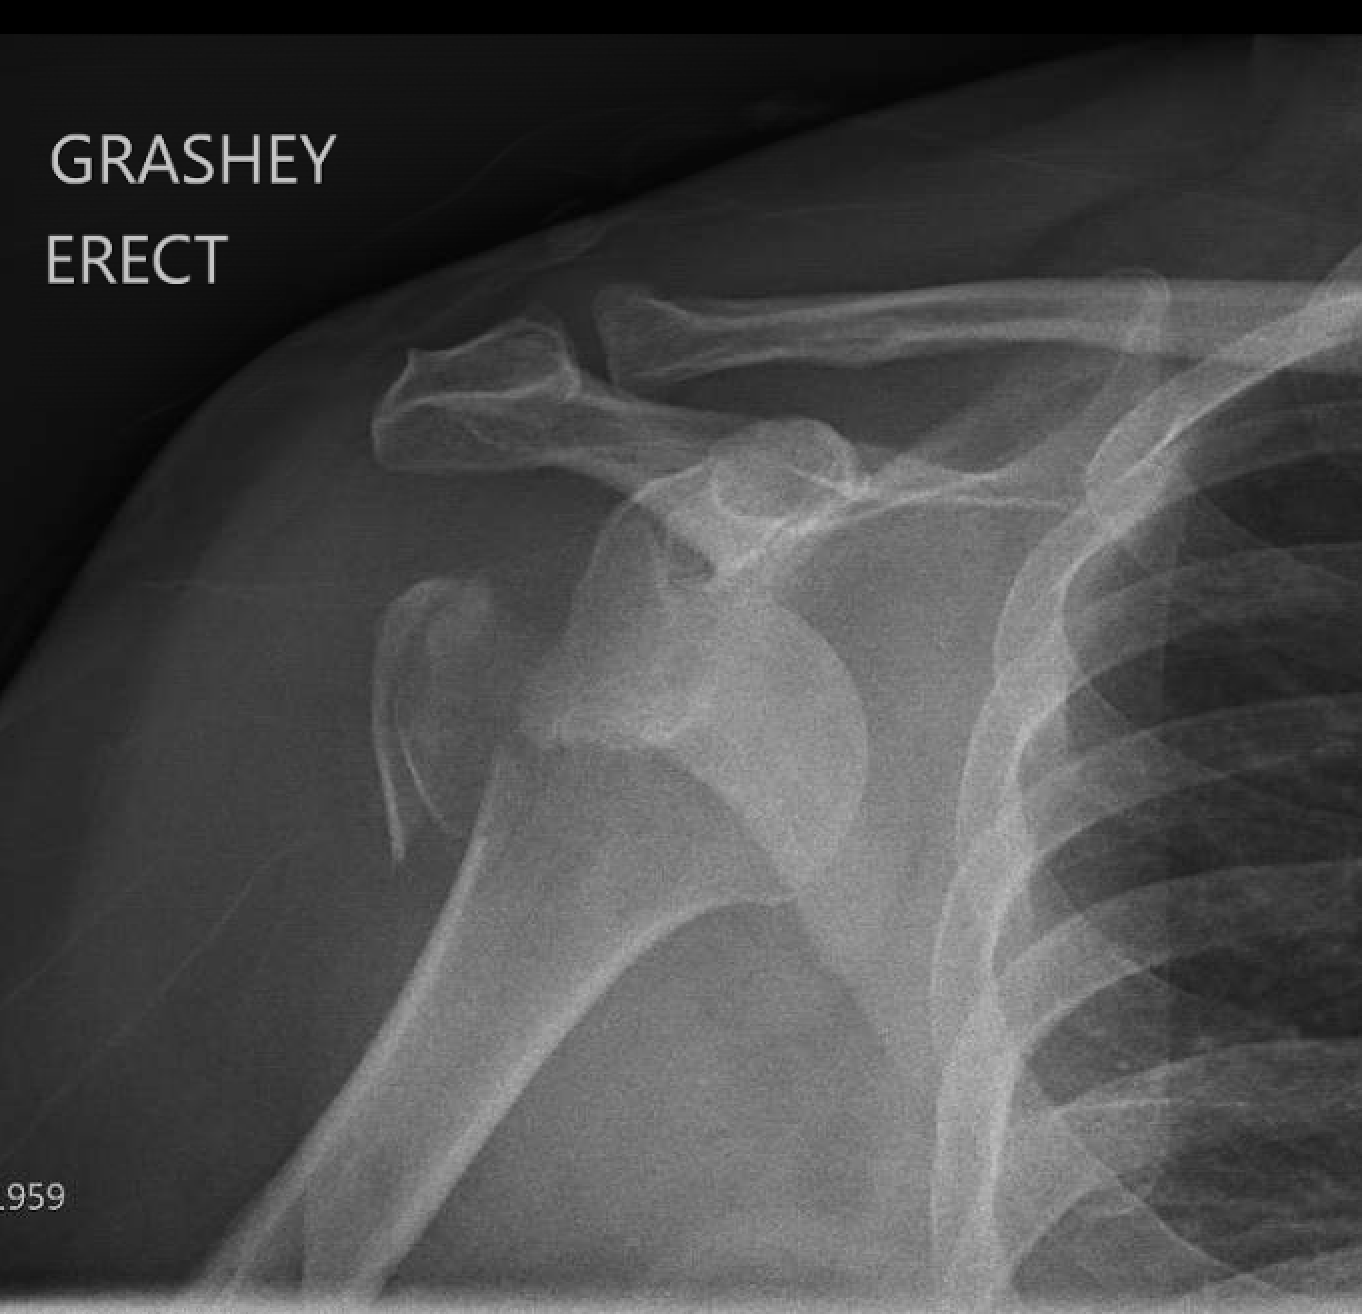

Shoulder and Elbow Surgery Locked proximal humerus fracture dislocation

Shoulder and Elbow Surgery Locked proximal humerus fracture dislocation Locked Elbow Surgery Removal of tight structures such as the joint capsule can improve elbow motion. If you are about to have elbow surgery, you may be wondering what to expect afterward. The grating is due to loss of the normal smooth joint surface. The locking is caused by. What is elbow fracture open reduction and internal fixation? Tommy john surgery, also known. Locked Elbow Surgery.

Shoulder and Elbow Surgery Locked proximal humerus fracture dislocation Locked Elbow Surgery Elbow locking may arise from injury,. Elbow locking can be associated with elbow stiffness and a decrease in range of motion (rom). Patients usually report a grating or locking sensation in the elbow. You may also have a sense of the elbow feeling like it might pop out of place. Removal of tight structures such as the joint capsule can. Locked Elbow Surgery.